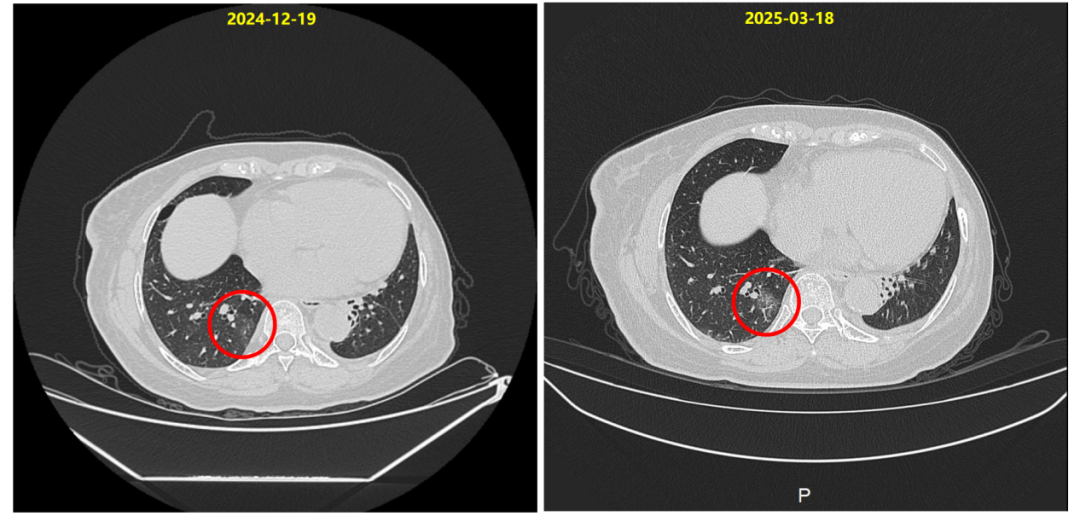

2025-03-18复查胸部CT提示:右肺下叶炎症考虑,局部较前明显,建议复查。

2025-03-19开始予甲泼尼龙(12mg po bid)治疗[等于0.5mg/(kg?d)泼尼松],10天后改为(8mg po bid)。

2025-04-09复查胸部CT:肺下叶炎症考虑,较前吸收,建议复查。

2025-04-10予甲泼尼龙(4mg po bid)治疗,2025-04-20至2025-04-30予甲泼尼龙(4mg po qd)治疗。

2025-05-05复查胸部CT:前片右肺下叶炎性灶基本吸收。

同时在T-DXd治疗过程中,患者于第11周期后出现右肺下叶炎症,经影像学评估确诊为1级间质性肺病。我们立即启动大剂量甲泼尼龙治疗,后逐步减量,ILD在22天内明显缓解,45天内基本消失。在确保ILD完全控制后,我们于2025年5月再启动T-DXd治疗,患者持续获益,影像学评估持续PR。该病例充分体现了在T-DXd使用过程中ILD这一关键不良反应的可管理性。通过早期识别、及时干预、规范减量和再挑战,患者不仅安全度过风险期,还继续从T-DXd治疗中持续获益。

同时,发生ILD是T-DXd治疗中需要关注的不良事件。本例患者接受T-DXd治疗过程中,于第11周期后出现了1级ILD,影像学表现为右肺下叶局限性炎症,无临床症状。团队在第一时间识别并启动激素干预(甲泼尼龙12mg bid),22天后复查CT显示炎症吸收,随后规范减量,约1个月后CT证实完全吸收。这一过程完全符合既往中华肿瘤杂志发表的《抗肿瘤药物相关间质性肺病诊治专家共识(2022)》[2]的分级管理原则。

ILD后T-DXd再挑战的可行性与安全性

本例患者ILD完全缓解后,于停药49天重启T-DXd治疗,剂量不变,后续随访多月余未见ILD复发,疗效持续。这一管理策略与2025年ASCO发布的真实世界研究数据高度一致[3]:该研究提示,患者出现1级ILD后,经规范治疗可尝试再挑战,患者仍能获得持久临床获益;同时,使用类固醇治疗可显著加速ILD影像学改善;而接受再挑战的患者中,复发性ILD的发生率较低,且大多为1级事件,未见5级事件发生。这些数据进一步支持了ILD患者应用T-DXd治疗再挑战策略的可行性与安全性。